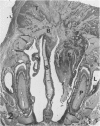

Charles River-CD Sprague-Dawley rats in 3 equal groups of 100 males and 100 females each were exposed to 12, 1, and 0 ppm of phenylglycidyl ether vapor for 24 months. Nasal tumors were first detected after 621 days' exposure at 12 ppm with an incidence of 11% in males and 4.4% in females. No nasal tumors were found at 1 ppm in rats exposed for 24 months. The nasal tumors, mostly epidermoid carcinomas, were derived from the respiratory epithelium and nasal glands, both of which revealed squamous metaplasia or dysplasia in the anterior nasal cavity. Most nasal tumors were confined to the anterior nasal cavity and occasionally invaded the dorsonasal bones and posterior nasal cavity. The undifferentiated glandular cells appear to differentiate to neoplastic squamous cells, because the ultrastructure of epidermoid carcinoma revealed traits of glandular cell differentiation in the neoplastic squamous cells. The features of glandular cell differentiation in the neoplastic squamous cells were intercellular or intracellular glandular lumens, secretory vesicles, mucus droplets, and intermediate cells showing both glandular and squamous differentiation. Squamous cells in the well-differentiated epidermoid carcinomas revealed abundant tonofibrils, desmosomes, glycogen particulates, and interdigitated cytoplasmic processes. These markers of squamous-cell differentiation were markedly reduced in the undifferentiated epidermoid carcinomas. The spindle-cell squamous carcinoma showed both squamous and fibroblastic-like differentiations. Some spindle cells had only fibroblastic-like differentiation, suggesting spindle-cell metaplasia of the squamous cells.